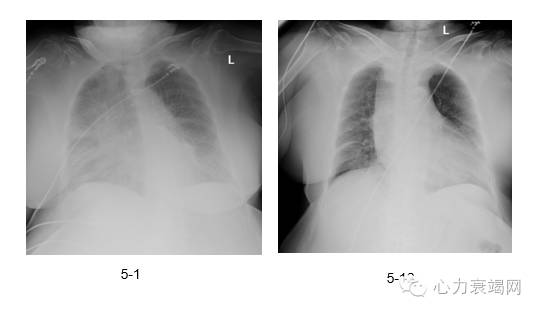

◆5-7超滤后呼吸困难症状明显减轻,夜间可以平卧,食欲改善,查体湿啰音消失

◆为了改善症状,使患者能够接受PCI,5-12日第二次超滤,后复查胸片明显改善

◆5-13行PCI治疗,因患者肾功能不全,当天24h给予800ml生理盐水水化

◆术后间断静脉利尿剂维持

胸片